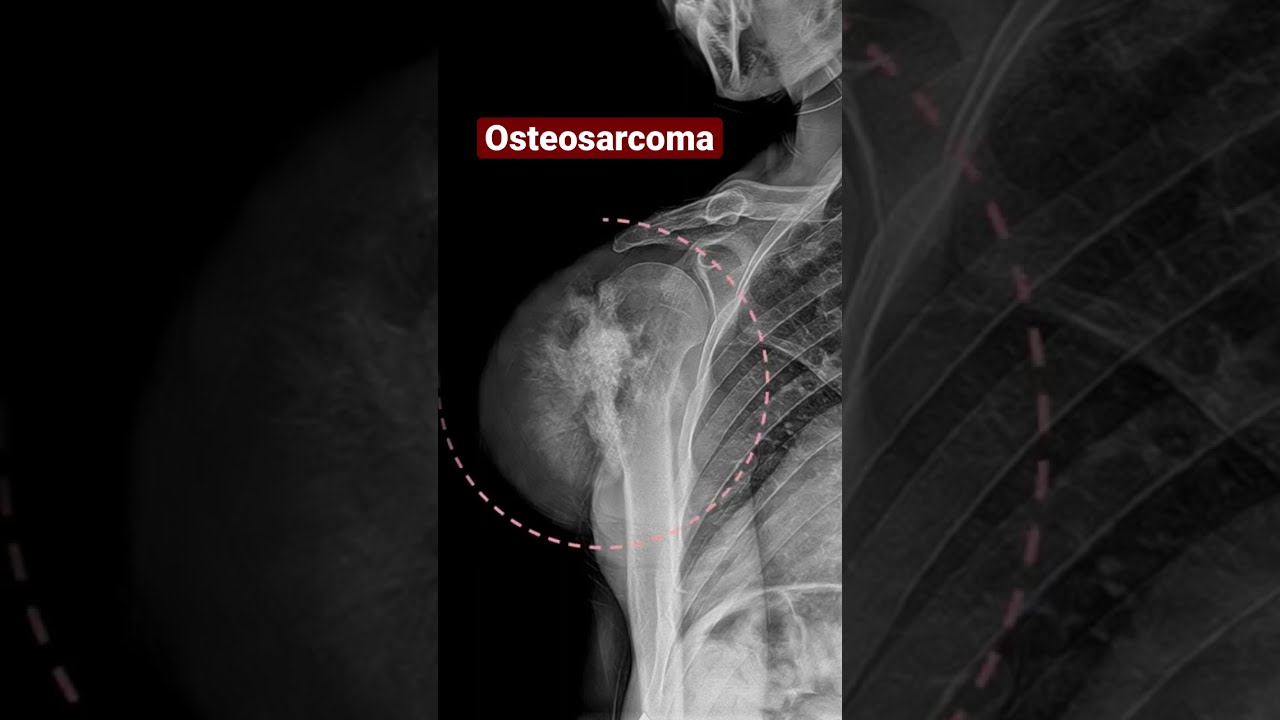

Рак Костей Симптомы И Проявление Фото

Рак Костей Симптомы И Проявление Фото 115 фото